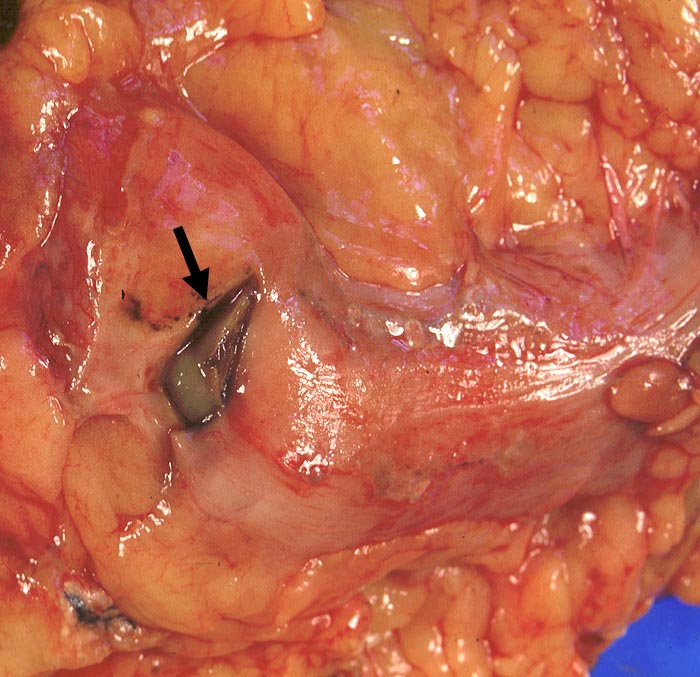

PathoPic ID 1408 - Magenulkus : freie Perforation

Magenulkus : freie Perforation

Blick auf den uneröffneten Magen.

►

Grosse Perforationsstelle. Nur geringe Peritonitis (matter Serosaüberzug).

Sekundärer Morbus Cushing bei Steroidtherapie von COPD. Alkoholabusus.